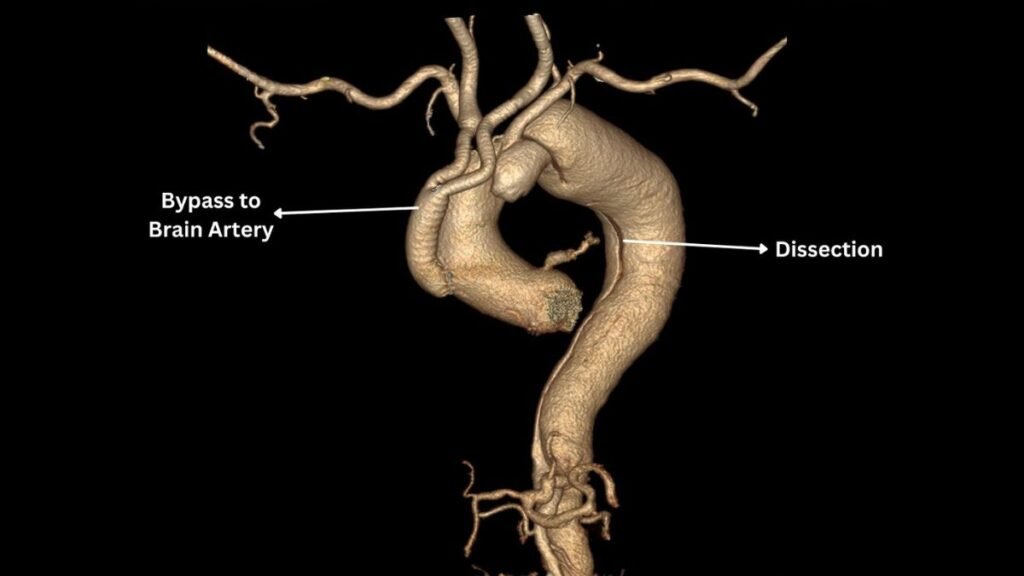

In a collaborative effort, Dr. Sudeep Singh Sidhu (Chief Cardiac Surgeon- Cardiac Surgery), a distinguished heart surgeon, and Dr. S. S. Bansal (Chairman and Managing Director SSB Hospital), a renowned cardiologist, devised an innovative solution: the Hybrid Procedure. The strategy involved a sequential approach where Dr. Sidhu initiated the debranching surgery, surgically connecting the brain and arm arteries to the ascending aorta before the dissection entry point. Following this, Dr. S. S. Bansal executed the endovascular-covered stenting of the aorta, effectively sealing the dissection.

Both phases of this intricate procedure were executed with precision and success, marking a significant achievement in the medical world. The patient demonstrated remarkable recovery post the dual procedures, showcasing the effectiveness of the Hybrid Procedure in addressing complex aortic dissections.